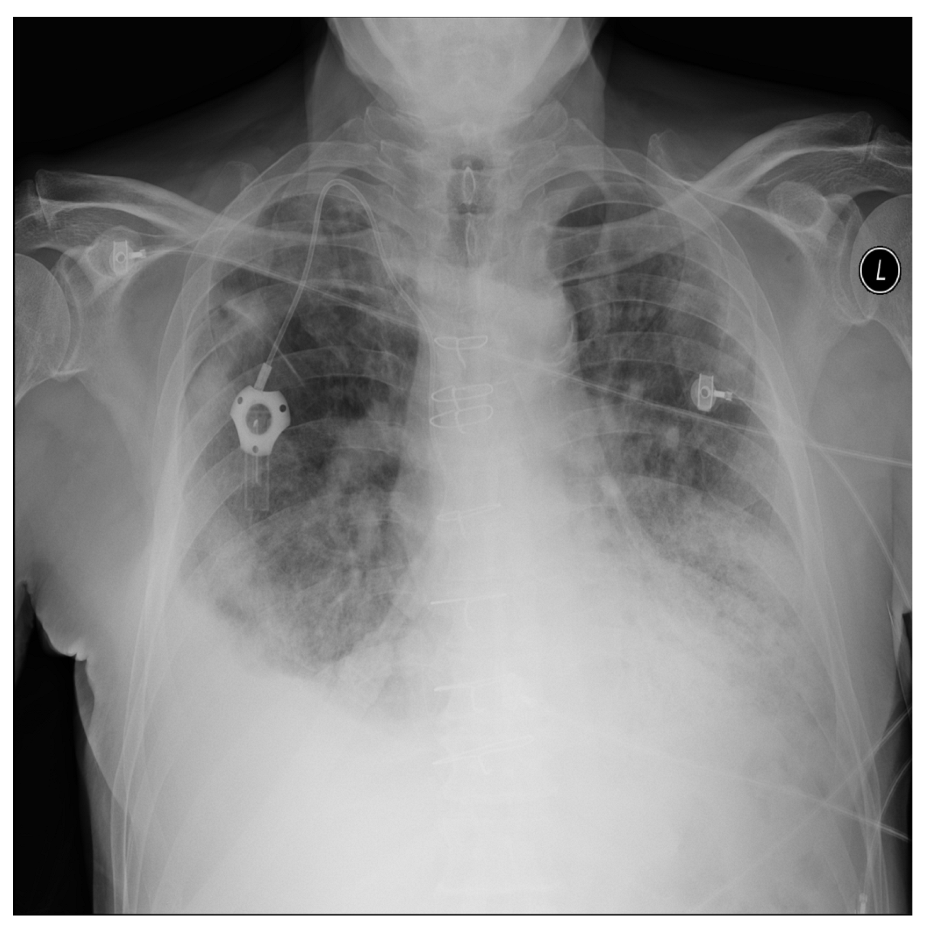

Figure 14 shows an example of typical chest X-ray images used for diagnosis. It can be observed that there are ground-glass opacities in the lungs of certain patients, which are identified using green rectangles. Pulmonary lobes and patchy consolidations are identified using blue ovals, indicating the presence of fibrosis or nodules. Doctors often use these features to determine whether patients are in a state of pneumonia, as well as its severity. Our model is designed to learn these features in order to achieve correct classification.

Figure 14. Analysis and diagnosis using patient CXR images.